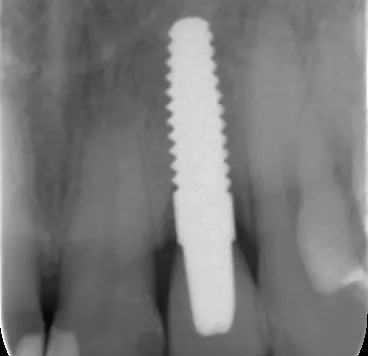

Implantate aus Reintitan mit rauen Oberflächen gelten als biokompatibel und finden nicht nur in der dentalen Implantologie, sondern auch zunehmend in der Orthopädie Anwendung. Mit der weltweit stetig wachsenden Anzahl inserierter Titanimplantate steigt allerdings auch die Rate sich entwickelnder Gewebeentzündungen um das Implantat. Der Periimplantitis wird in der wissenschaftlichen Literatur zunehmend Aufmerksamkeit geschenkt, gleichwohl die Angaben zur Prävalenz auch erheblich schwanken. Die in einer Metaanalyse gewichteten Mittelwerte betragen für die periimplantäre Mucositis 43 % und für die Periimplantitis 22 % [2]. Es besteht eine Korrelation von Periimplantitisprävalenz und verkürzter Implantat-Funktionszeit.

Da die periimplantäre Osseointegration als eine immunologisch modulierte Interaktion mit dem implantären Fremdmaterial gesehen wird, bedeutet der marginale Knochenabbau den Verlust des „foreign body equilibrium“, einer ausgeglichenen, balancierten Fremdkörperreaktion [3]. Die prädisponierenden Faktoren für eine periimplantäre Entzündung oder einen daraus resultierenden Implantatverlust sind hinreichend beschrieben worden. Neben Knochenqualität, Art des Implantatsystems, Fehlpositionierung und Fehlbelastung des Implantates, Immunkompetenz des Patienten sowie negativen Gewohnheiten wie Rauchen wird in erster Linie der Biofilmausbildung als mikrobielle Ursache für eine periimplantäre Entzündung eine ursächliche Bedeutung beigemessen.

Die Erfolgsrate für die Zirkonoxidimplantate der neuen Generation ist vergleichbar mit der bei Titanimplantaten [23-26]. Einteilige Zirkonoxidimplantate zeigen in klinischen Untersuchungsreihen hinsichtlich ihrer Osseointegrationsfähigkeit im Vergleich zu Titanimplantaten nicht nur ebenso gute Erfolge, sondern sie haben auch noch Vorteile in Bezug auf die Weichgewebeakzeptanz [27].

Eine prospektive randomisierte klinische Vergleichsstudie von zweiteiligen Zirkonoxid- und Titanimplantaten als Einzelzahnersatz an einer kleinen Kohorte (14 Zr- und 14 Ti-Implantate) ergab nach einem Zeitraum von 80 Monaten keine signifikanten Unterschiede in Bezug auf Belastungsstabilität in Funktion und untersuchte parodontale Marker [28].